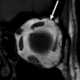

Bowed femur